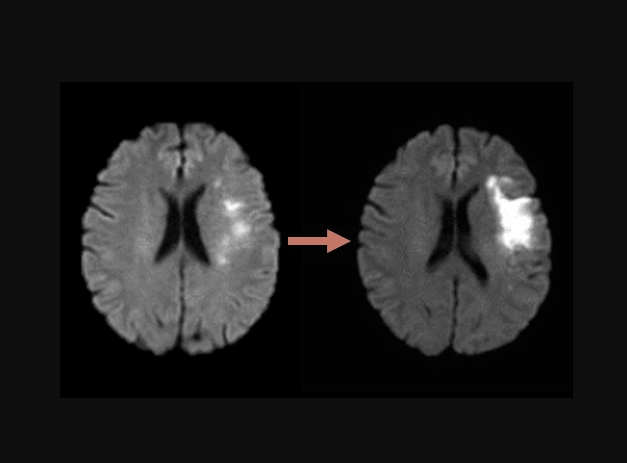

A stroke happens in two main ways. The first is an ischemic stroke, caused by a blockage in a blood vessel supplying the brain. The second is a hemorrhagic stroke, which occurs when a blood vessel ruptures and causes bleeding in the brain. Both types can affect the right hemisphere and lead to significant neurological damage if not treated quickly.

Diagnosing a right side brain stroke involves a combination of physical examination and imaging tests such as CT scans or MRI scans. Doctors assess symptoms and determine the type and location of the stroke.